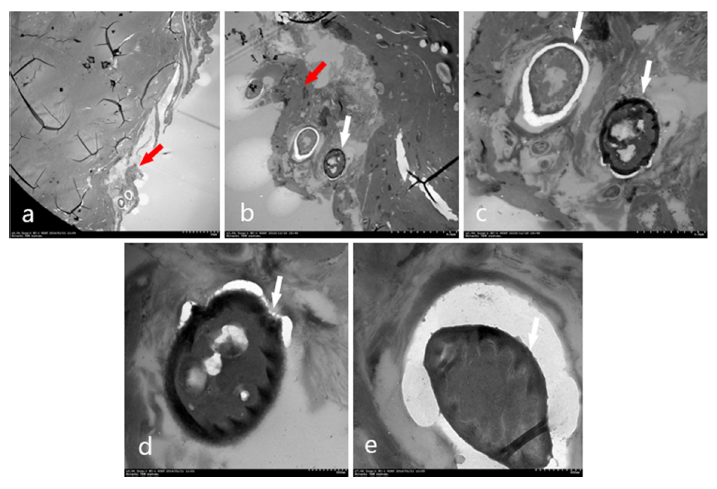

马拉色菌酵母除了黏附到毛发根部表皮细胞表面和细胞间,是否侵入到角质细胞内呢?这就需要通过超薄切片后用透射电镜观察。不如所料,我们在透射电镜则观察到了发根部外毛根鞘的角质形成细胞中含有马拉色菌酵母细胞(图11、12)。

图11 透射电镜观察到AGA患者毛根部毛根鞘至外毛根鞘之间的结缔组织鞘(紫色箭头)内嵌有马拉色菌酵母细胞(绿色箭头),细胞壁内侧有马拉色菌特有的锯齿状结构。a×300, b×1000, c×4000, d×5000

图12 透射电镜观察到AGA患者毛囊外包绕的毛囊结缔组织鞘(红色箭头)内嵌有马拉色菌酵母细胞(白色箭头),细胞壁内侧有马拉色菌特有的锯齿状结构 a×500,b×1500,c×4000,d、e×6000